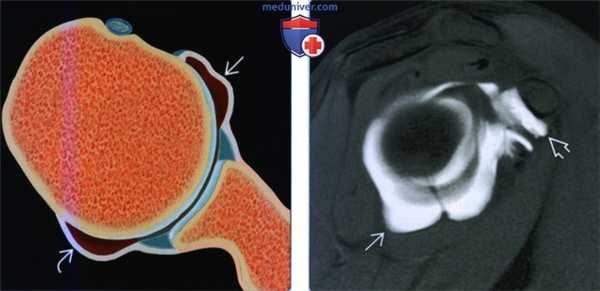

(Слева) На рисунке показана растянутая передняя и задняя капсула без разрыва губы, как наблюдается у пациентов с разнонаправленной нестабильностью. Разнонаправленная нестабильность часто является семейным заболеванием.

(Справа) На косой сагиттальной МР-артрограмме Т1ВИ визуализируется растянутая передняя, задняя и нижняя капсула. Кроме того, наблюдается растяжение капсулы ротаторого интервала. Упражнения на усиление ротаторной манжеты и восстановления оптимального нейромышечного контроля могут ослабить симптомы.